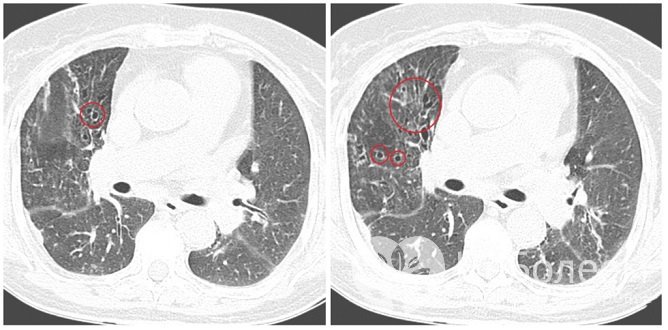

Разновидности бронхоэктазов по форме расширения бронхов

рентгенография легких [выявляются деформация и усиление легочного рисунка, ячеистый легочной рисунок в области нижних сегментов, тонкостенные кистоподобные просветления (полости), иногда с жидкостью, уменьшение объема (сморщивание) пораженных сегментов, повышение прозрачности здоровых сегментов легкого, «ампутация» корня легкого, наличие косвенных признаков бронхоэктатической болезни];

бронхография с контрастным веществом (определяются расширение бронхов различной формы, их сближение и отсутствие заполнения контрастным веществом ветвей, располагающихся дистальнее бронхоэктазов);